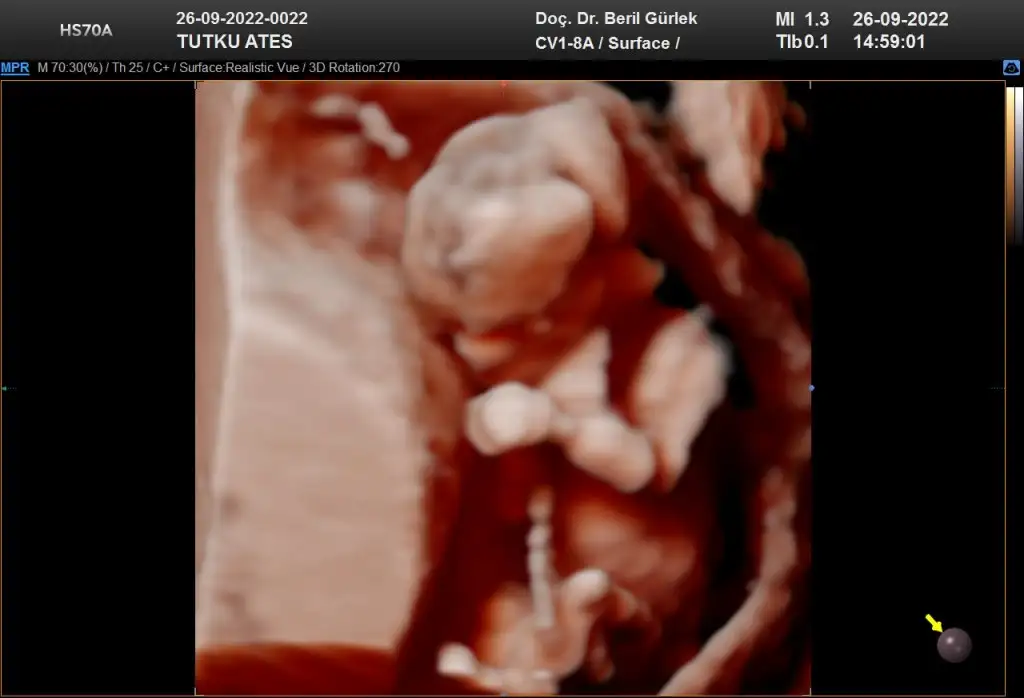

Teşekkür ederim ben de öyle düşünüyorum hayırlısı olsun:)) bu başka bir fotoğraf 11+3

• IMG_20220924_143556.webp

5,8 KB · Görüntüleme: 1.068